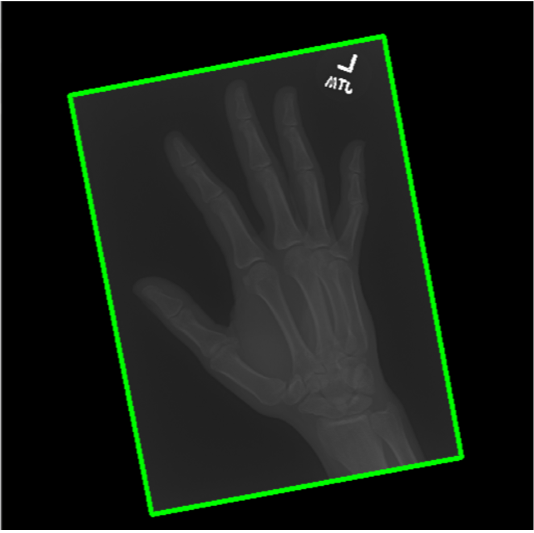

The first step in our pipeline is to detect the X-ray image carrier in the image. To this end, we apply OpenCV’s contour detection using Otsu binarization [14], and retrieve the minimum size bounding box, which does not need to be axis-aligned. This works sufficiently well as long as the majority of the image carrier is within the image (cf. Figure 3). However, the approach might fail for heavily tilted images or those where larger parts of the image carrier reach beyond the image border.

Hand Localization

To further improve the detection of hands, and in particular split the images where two hands are depicted on one image, we manually labeled approximately 150 bounding boxes in the images. Using this small dataset, we fine-tune a pre-trained single shot multibox detector (SSD) [12] with MobileNet as taken from TensorFlow. An exemplary results can be seen in Figure 3.